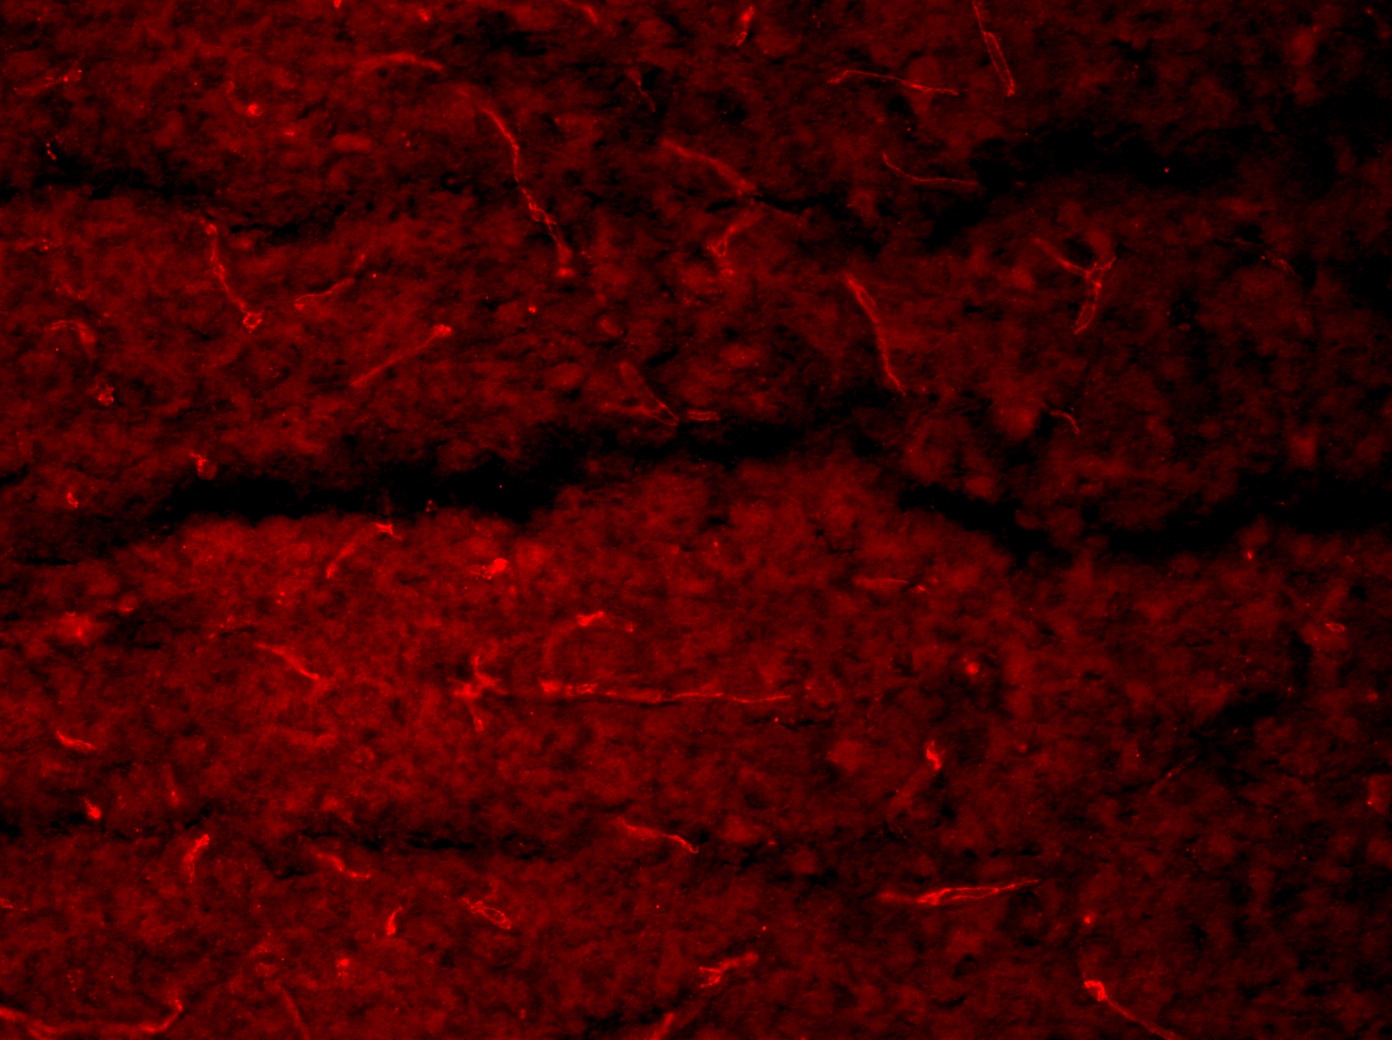

Dilution 1:200

10um think hearts sections. Fixed with 4% PFA at RT for 10mins, permeabilized using 0.3% triton for 30mins at RT followed by 1% BSA block. Incubated with Goat Podocalyxin (1/100 concentration) at 4’C – O/N. Washed using 1xPBS, Detected using Donkey anti-goat alexa 568 (1/200 concentration). Washed and mounted using prolong antifade reagent with DAPI